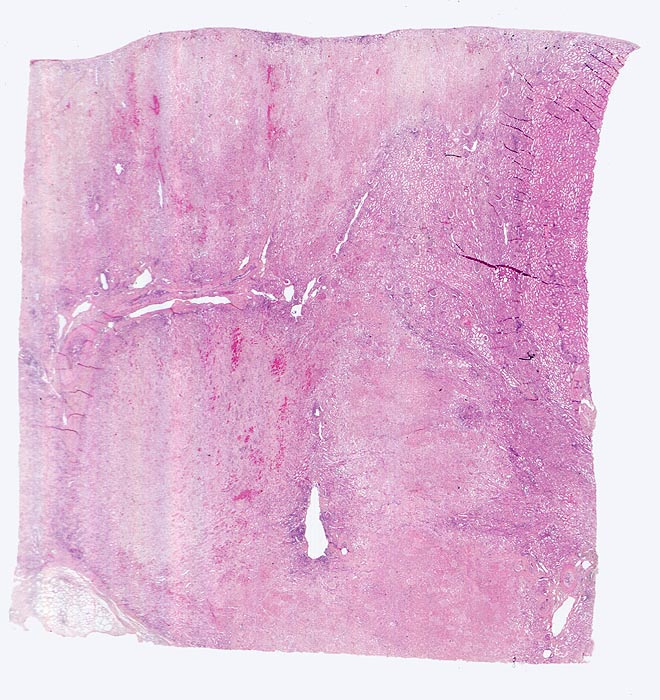

Morphologie:

Je nach Grösse des verschlossenen Gefässes sind unterschiedlich grosse (wenige Millimeter bis mehrere Zentimeter) solitäre oder multiple scharf begrenzte Herde erkennbar. Nach etwa einer Woche imponiert der akute Infarkt als gelber erhabener Bezirk mit 2-5mm breitem rotem Randsaum. Subakute Infarkte bilden flache homogene rote Herde. Nach Monaten bildet sich eine scharf begrenzte weisse Narbe aus. Infolge unterschiedlicher Kollateralversorgung z.B. via Arteria spermatica oder ovarica führt der Verschluss der Arteria renalis nicht immer zur Totalnekrose. Das Endstadium grosser Infarkte bildet die grob gebuckelte Infarkt-Schrumpfniere.

Akute Infarkte bilden histologisch scharf begrenzte kokardenförmig aufgebaute Herde mit zentraler Koagulationsnekrose umgeben von einem Saum neutrophiler Granulozyten. In der Peripherie ist das partiell geschädigte Gewebe ödematös hämorrhagisch und enthält dilatierte hyperämische Gefässe. Die Nekrose wird durch neutrophile Granulozyten und Makrophagen abgebaut und durch Granulationsgewebe ersetzt, welches zu einer gefässarmen Narbe schrumpft. Die äusserste Rindenzone bleibt infolge der Kollateralversorgung durch Kapselgefässe oft vom Infarkt ausgespart. Infarktnarben können wie alle Narben verkalken.